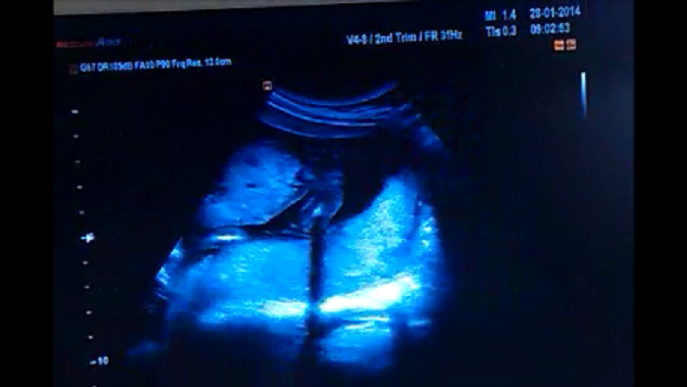

Našla jsem před pár dny tuto hezky rozjetou diskuzi... a líbí se mi, jak všechny držíte pospolu a vzájemně se podporujete... Také patřím termínově k vám. TP mám 28.6. a čekám čtvrté dítko

Doma mám 3 klukánky a od začátku tuším, že i prcek v bříšku je další fotbalista. Můj dr. mi to však i přes utz potvrdít nechce... takže jsem si říkala, že spousta z vás, už má několik UTZ za sebou a zná pohlaví miminek, že byste mi mohli pomoci s odtajněním ...